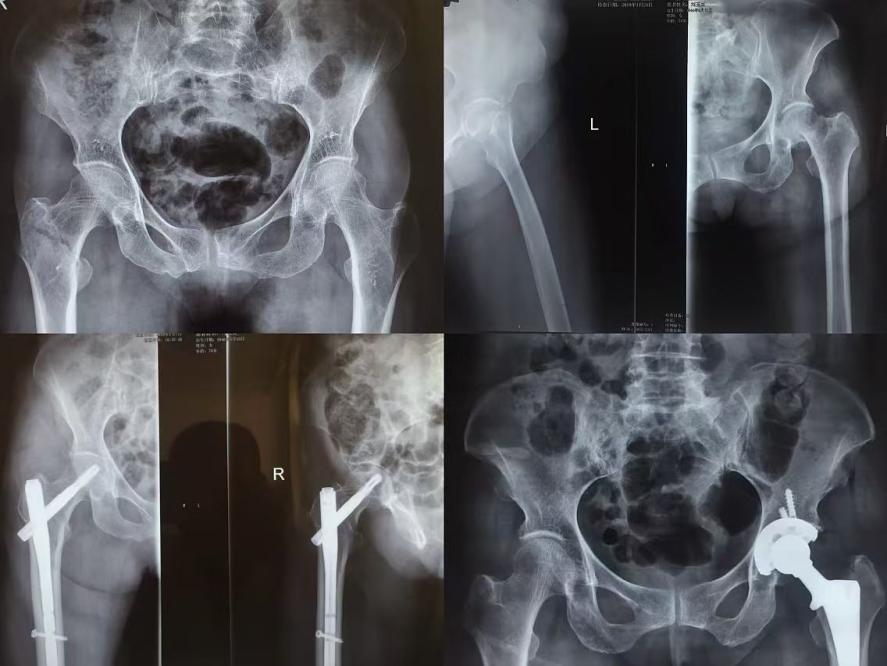

股骨粗隆间骨折

老年患者通常因为地滑摔倒所致“窝骨骨折”,既是老年患者“躺着等走”,亦是每个家庭的痛苦,不愿老人长期卧床遭受疼痛折磨,照料老人的劳累。“窝骨骨折”部分为股骨粗隆间骨折。随着医学的发展,年龄已不再是手术的禁忌症,但是对于80岁以上的高龄并且合并不同程度内科疾病的患者手术风险依旧很高,PFNA(股骨近端抗螺旋型髓内钉)固定以安全有效、微创的固定系统,其整体稳定和成角稳定性使骨折固定更牢固。手术切开仅5cm左右,有效规避了创伤大、失血量大等不足,降低了患者手术风险。髋关节置换术更是针对于此类患者更早健康行走的希望,髋关节置换术后3天后即可辅助助步器进行行走功能锻炼。有效避免了患者长期卧床褥疮、坠积性肺炎及血栓形成等一系列卧床并发症,提高患者生活质量。